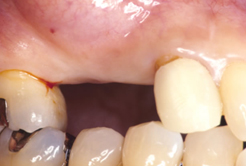

インプラント治療の前に(骨の環境整備)右上小臼歯部

右上小臼歯部

右上の1番は抜歯となりました。 抜歯後に骨造成(GBR)を行います。